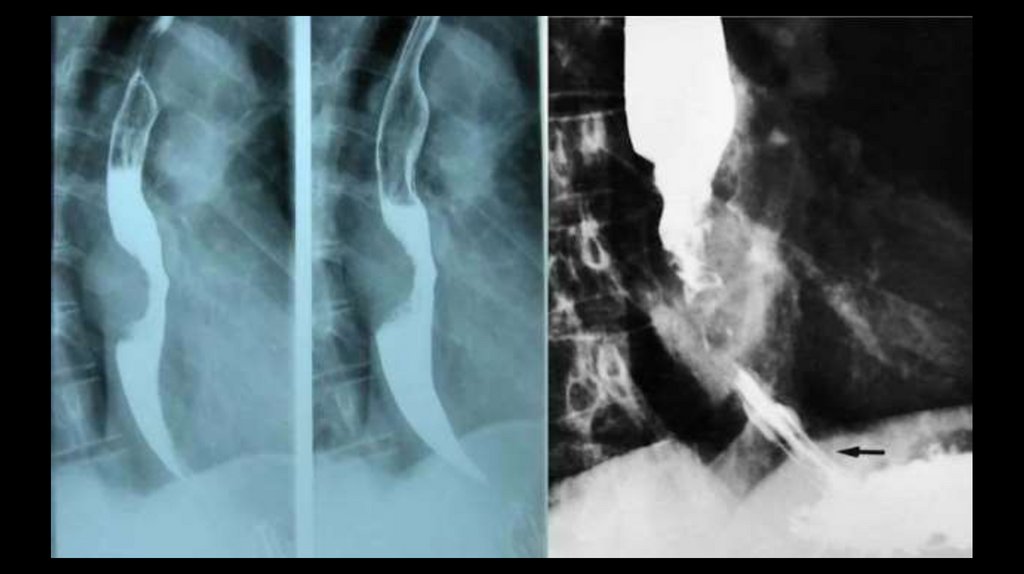

• «Пищевод щелкунчика» (синоним — сегментарный спазм пищевода) —

нарушение моторики пищевода, при котором наблюдаются сокращения

дистальной части пищевода высокой амплитуды и большой длительности.

Некоторые симптомы: дисфагия, сильная боль в груди. Заболевание может

протекать бессимптомно.

• «Пищевод щелкунчика» — доброкачественное, непрогрессирующее

заболевание, не приводящее к серьёзным осложнениям.